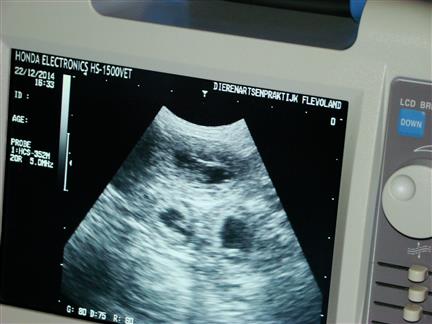

niet alle foto's zijn even duidelijk |

| maar in de donkere ronde vlekken |

zie je witte lijntjes |

| en dat zijn .......... de puppies :-) |

ook zijn de hartjes al aan het kloppen, allemaal prachtig om te zien |